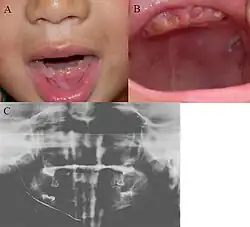

Oral photographs from an individual with Dentinogenesis imperfecta | |

People with this condition have abnormal enamel, short and narrow roots, and can lack nerves. This condition can cause teeth to be discolored (most often a blue-gray or yellow-brown color) and translucent, giving teeth an opalescent sheen.[2][3][8][5][9] Teeth are also less mineralized than normal, making them prone to rapid wear, breakage, and loss.[2][3][4][5][8] These problems can affect primary (baby) teeth alone, or both baby teeth and permanent (adult) teeth, with the primary teeth usually more severely affected.[5][8]

- Discolored teeth - teeth may be amber, brown, blue or opalescent

- Bulbous shape to the tooth crown due to cervical constriction

- Tooth wear/Non-carious tooth surface loss (NCTSL) - due to the poorly mineralized dentin, the enamel of the tooth is unsupported and subsequently shears or chips off as it is subjected to occlusal (biting) forces. This exposes the underlying less mineralized dentin which is less resistant to wear. Therefore, features of abrasion and attrition may become apparent.

The primary (baby) teeth are usually more severely affected than permanent (adult) teeth.[3][5][8]

Enamel is usually lost early because it is further inclined to attrition due to loss of scalloping at the dentinoenamel junction (DEJ). It was suggested that the scalloping is beneficial for the mechanical properties of teeth as it reinforces the junction between enamel and dentin.[15] However, the teeth are not more susceptible to dental caries than normal ones.

Note that, although dentin exposure is a common clinical finding, individuals with dentinogenesis imperfecta usually do not experience tooth sensitivity as the exposed dentin is typically sclerosed (hardened), thereby appearing glassy/shiny.[2]